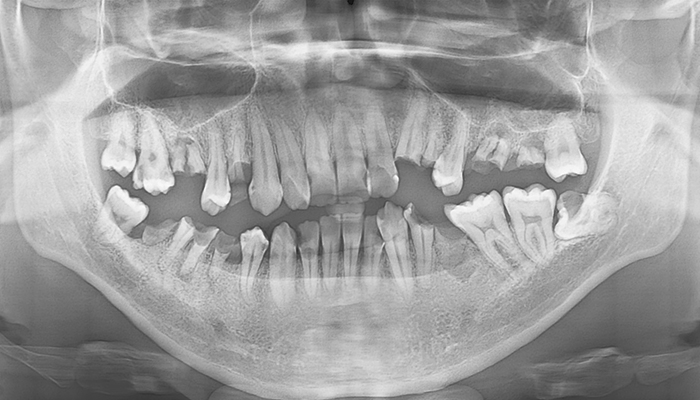

【50代男性】前歯のインプラント症例

「事故で下の歯を欠損したのを治したい」

治療前

治療後

CT画像

| 主訴 | 事故で怪我したため、欠損した箇所を治したい |

| 治療期間 | 約9ヶ月 |

| 治療費 | 合計1,600,000円(税別) 下の歯だけのインプラント:100万円(税別) |

| 治療内容 | 事故で骨内に入り込んだ歯を整復して、修復治療・欠損した箇所についてはインプラント治療を行いました。 ・GBRで骨造成を行い、インプラント2本を埋入し、ブリッジにて治療。 ・エクストリュージョン(歯根挺出術)。 |

| 治療のリスク | 前歯のインプラント治療では、審美性の問題や骨密度不足によるインプラントの不安定、神経損傷や感染のリスクがあり、術後の腫れや痛みも発生する可能性があります。 |